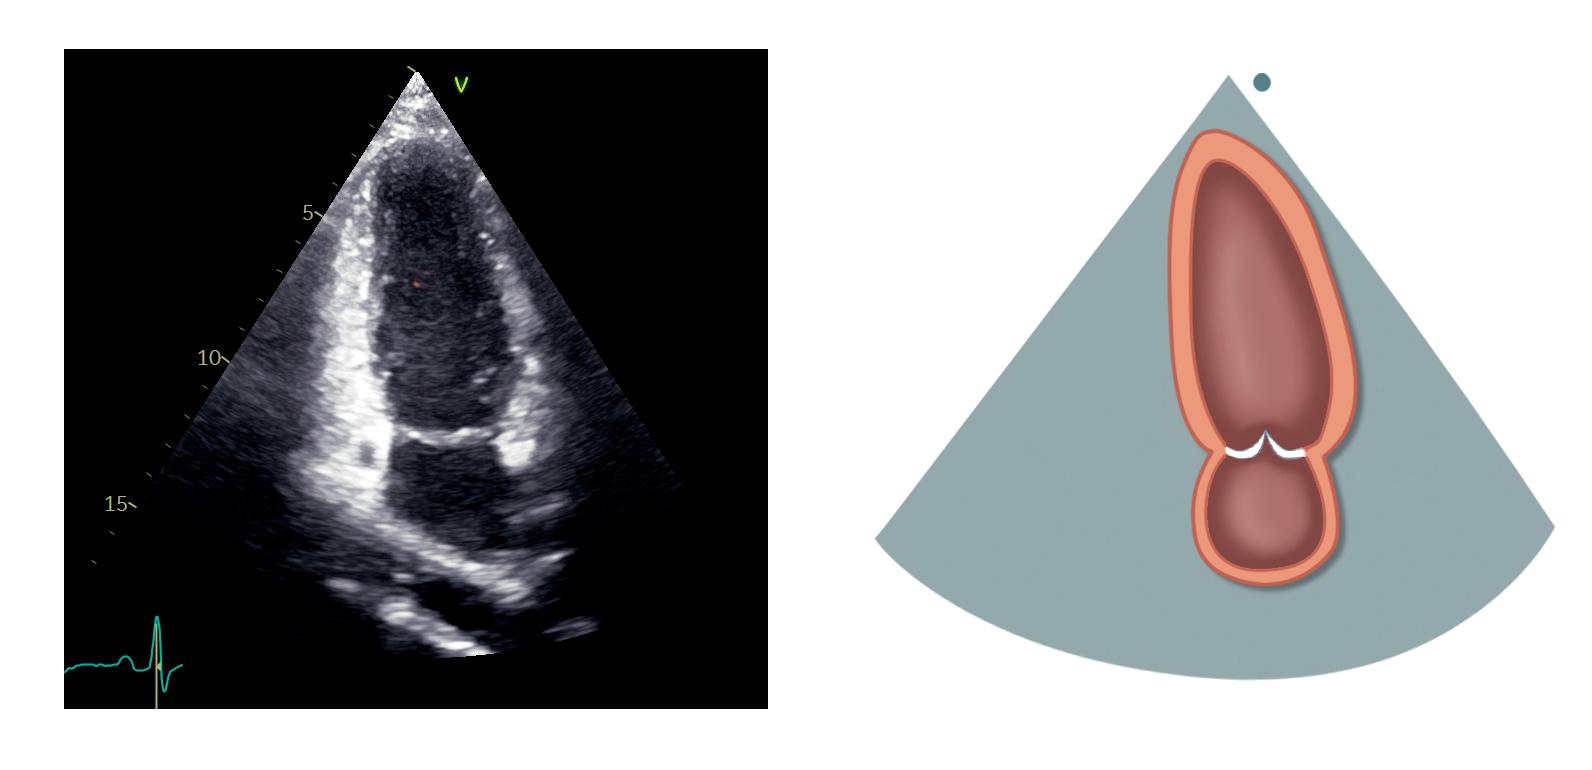

Figur 1.5: 2D-ekkokardiografi av hjertet i apikal 4-kammerprojeksjon Venstre ventrikkel er kammeret øverst til høyre Legg merke til at ventrikkelveggen er særlig tykk mot apex (piler) Dette er et eksempel på apikal hypertrofisk kardiomyopati (HCM) med det såkalte ace of spades-tegnet Figur 1.4: M-modusekkokardiografi i parasternal langakseprojeksjon med markørlinjen gjennom venstre ventrikkel Eksempelet viser måling av ventrikkelens veggtykkelser og indre diameter, som muliggjør estimering av blant annet ventrikkelmassen